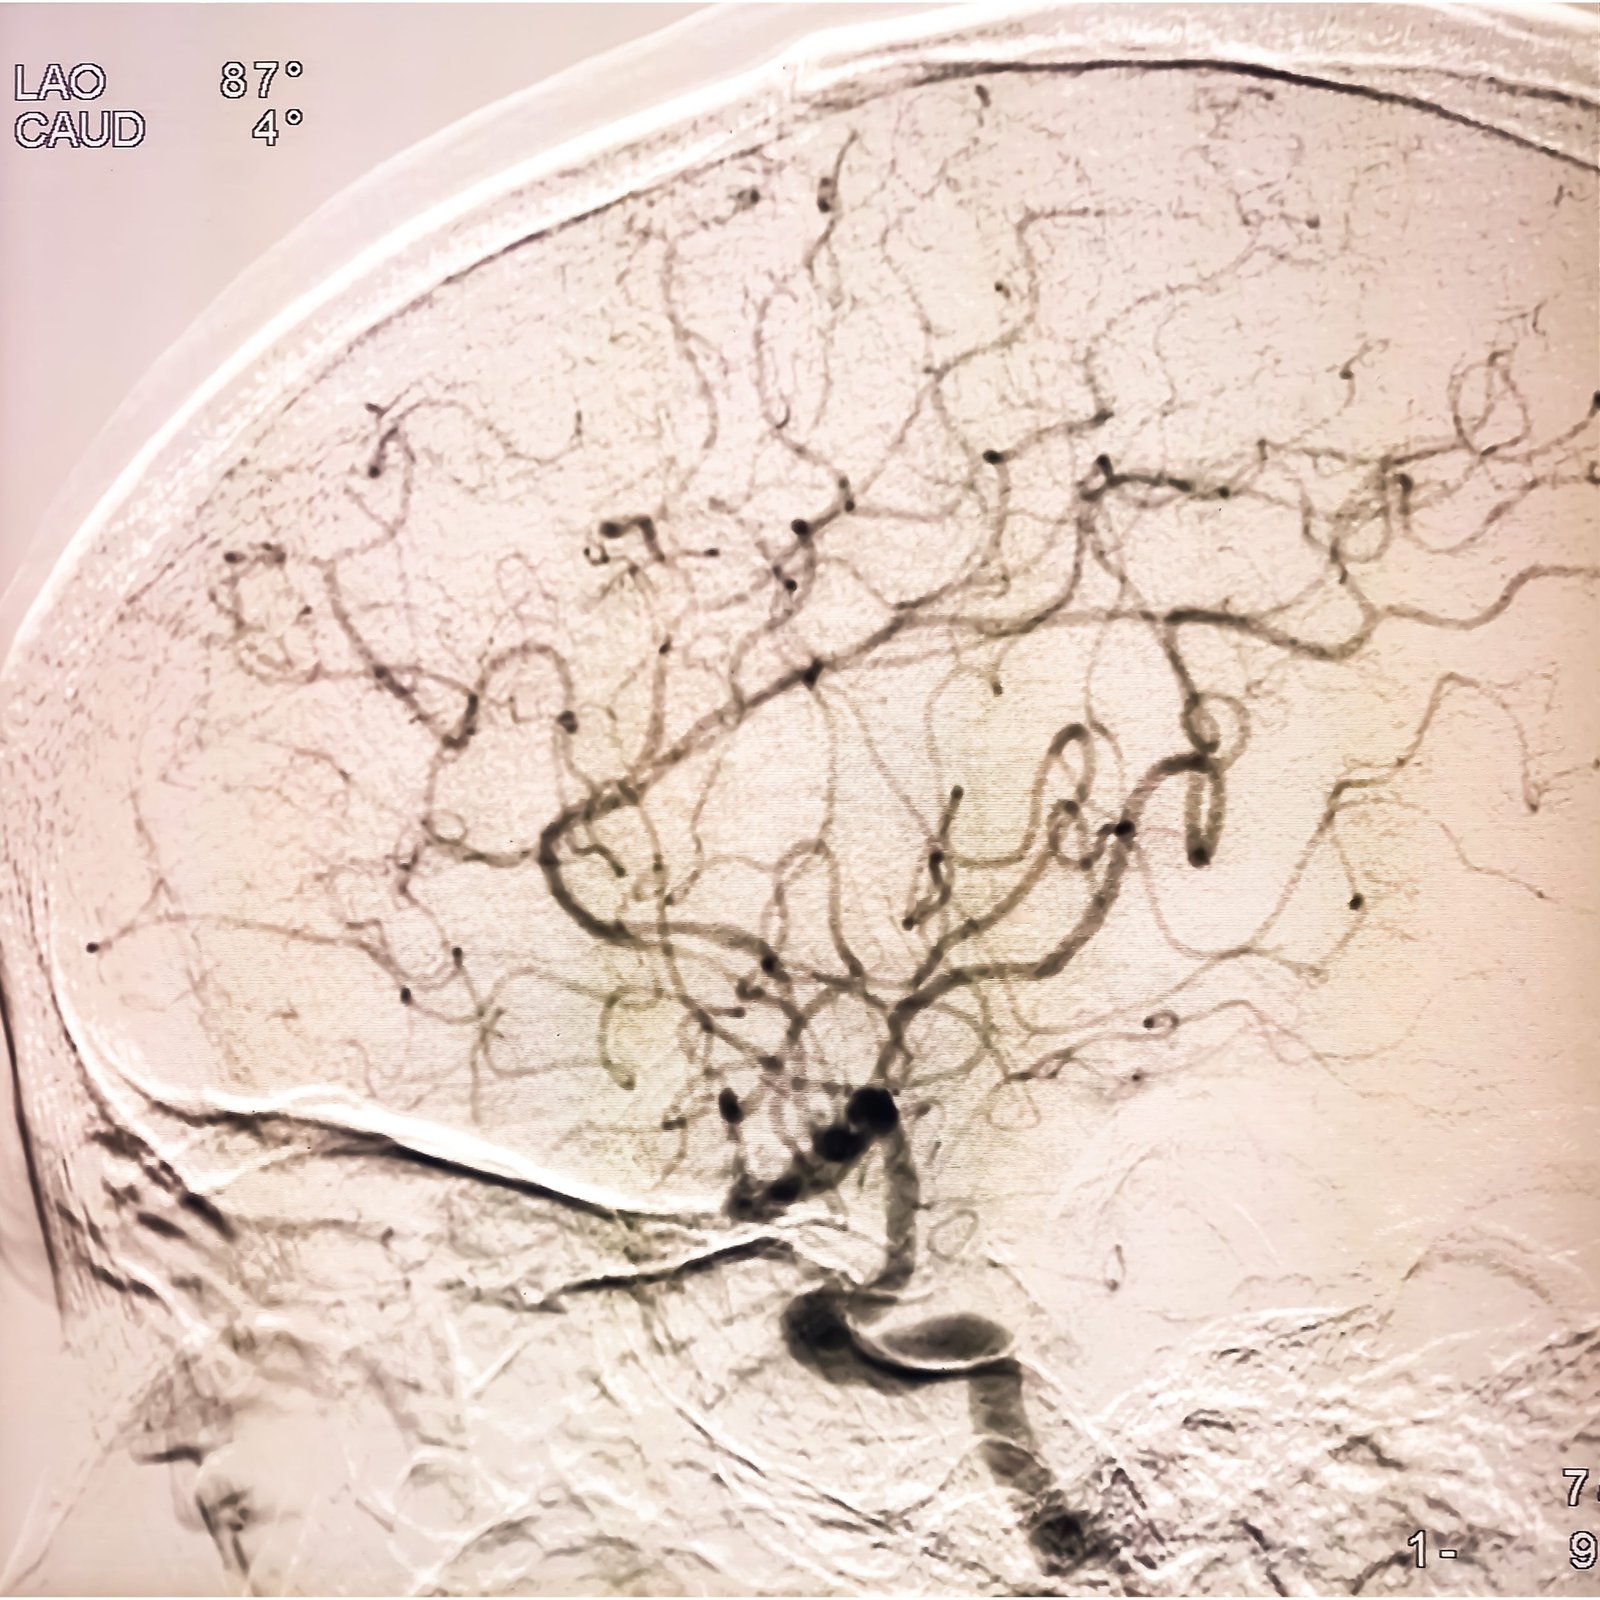

Angiography, angioplasty, stenting, thrombolysis, thrombectomy, embolisation, and aneurysm repair are used to restore blood flow or control abnormal circulation without open surgery.

Interventional Radiology focuses on targeted procedures performed under imaging guidance, allowing the team to reach tumours, bleeding vessels, blocked ducts, narrowed arteries, thrombosed veins, and painful lesions with far less disruption than conventional surgery.

The department is presented as an innovation-led unit that combines CT, ultrasound, and DSA guidance to diagnose and treat disease through targeted procedures that often avoid open surgery.